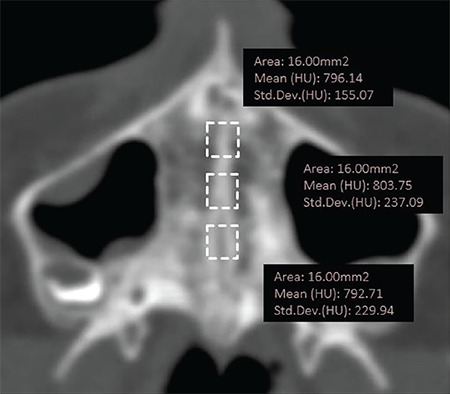

Methods: A Digital Imaging and Communication in Medicine dataset of 20 patients (mean age: 15.55 years) prior (T0) and after (T1: 3.5±0.5 months) to RME were retrieved from the archive and analyzed. Bone density values of midpalatal suture (MPS), zygomaticomaxillary suture (ZMS), zygomaticotemporal suture (ZTS), pterygopalatine suture (PPS), and transverse palatine suture (TPS) were measured. The cervical vertebral maturational stages (CVS) were examined. The linear distances between the most lateral points of the piriform apertures were measured as the anterior reference, and the medial margins of the greater palatine foramina on the axial slice were chosen as the posterior reference. The difference at T1-T0 was calculated as the skeletal response to RME at anterior and posterior skeletal references. Spearman's rho rank and Kruskal-Wallis tests were used.

Results: Mean density values of ZMS, PPS, ZTS, TPS, MPS-Anterior, and MPS-Posterior were 922.81, 807.44, 753.83, 640.77, 661.13, and 604.59 HU, respectively. Mean linear changes in anterior and posterior skeletal expansion were 2.93±1.78 and 1.93±2.52 mm. There was no significant relationship between maturation indicators and skeletal response. Significant relationships were found between CVS and MPS density and CVS and circummaxillary suture average density (p≤0.05).